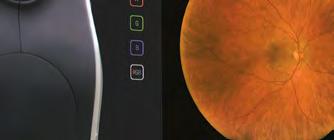

Wide-field retinal imaging shouldn't mean compromising on space or budget. The brand new Visionix VX625 delivers 220° Ultra Wide Field (95% retina coverage) revealing retinal diseases and pathologies that standard 45° imaging can miss. All delivered in a compact, all-in-one design that fits seamlessly into any practice.

Auto-montage seamlessly combines two images to capture 220° and over 95% of the retina in a single image.

176º single image with VX625

45º fundus image

Red Channel Green Channel Blue Channel